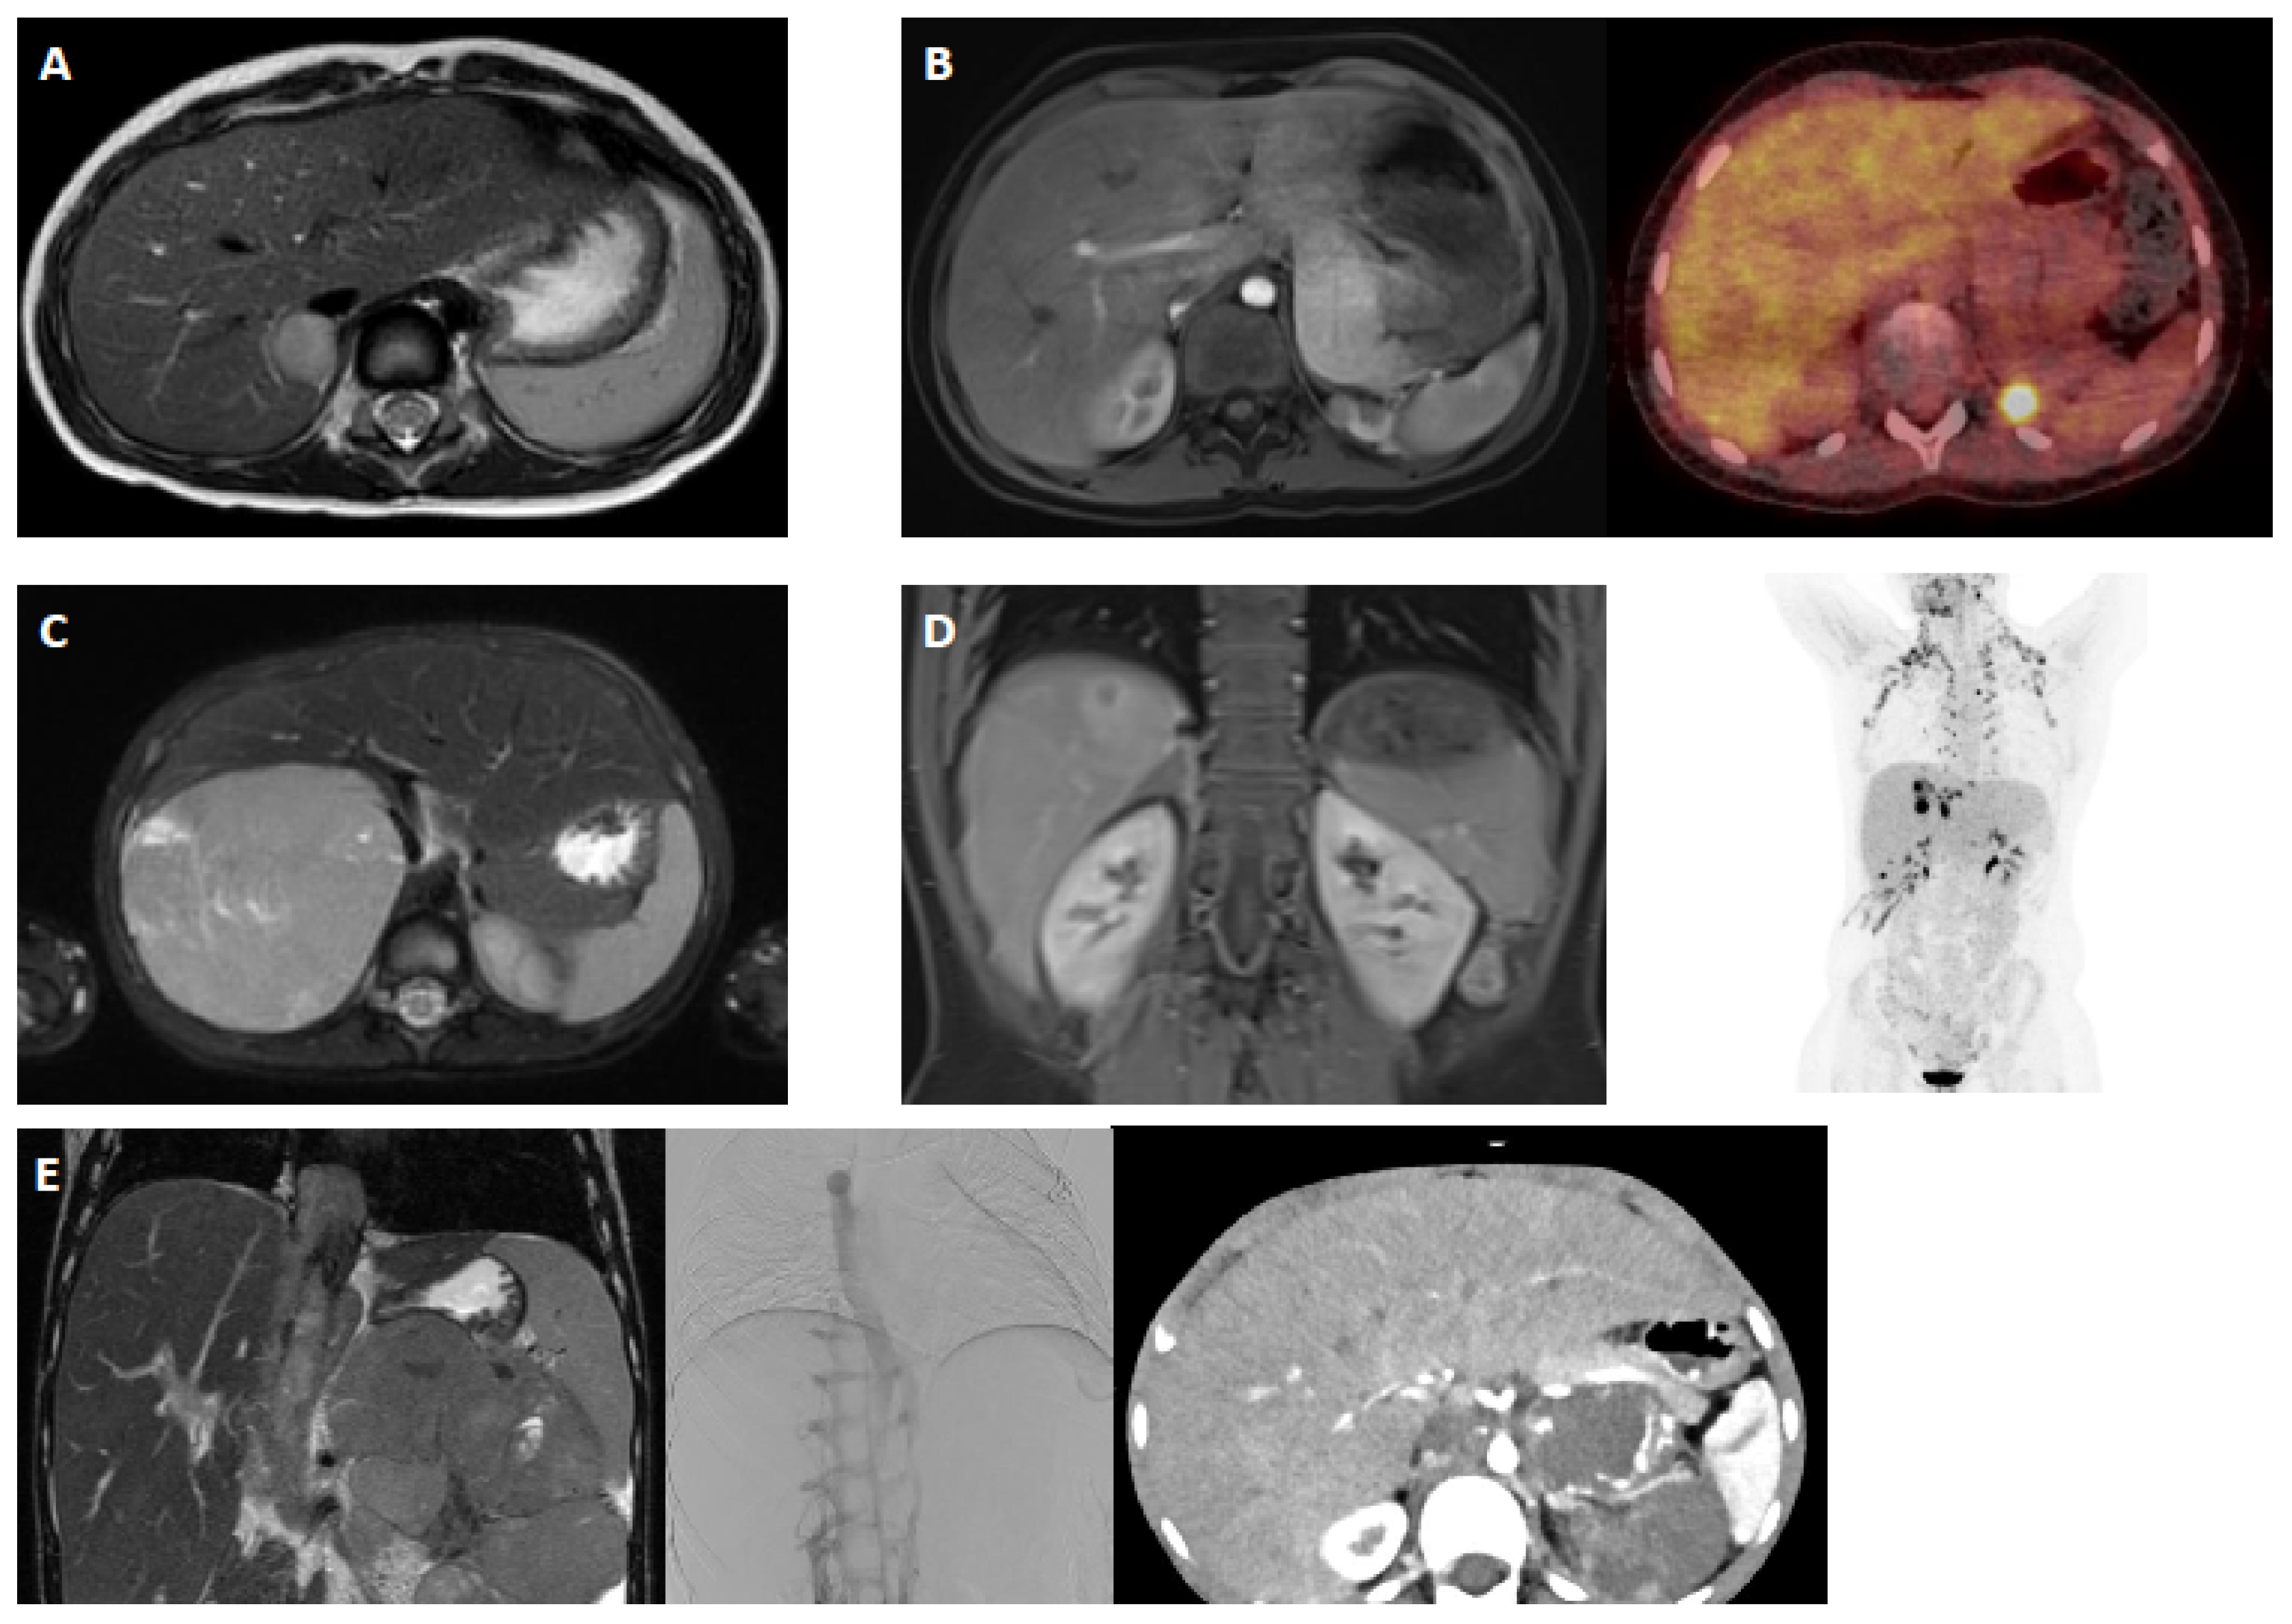

3.2. Case 1: Localized Right-Sided Adrenocortical Tumor with Androgen Secretion, Initial Diagnosis (For Case 1 Details See Table 1 and Figure 1A)

3.3. Case 2: Second Local Relapse of Stage IV Left-Sided Adrenocortical Carcinoma with Androgen Secretion (For Case 2 Details, See Table 1 and Figure 1B)

3.4. Case 3: Right-Sided Adrenocortical Tumor of Stage III with Androgen Secretion, Initial Diagnosis (For Case 3 Details, See Table 1 and Figure 1C)

3.5. Case 4: Stage IV Left-Sided Adrenocortical Carcinoma, Cortisol-Secreting, with Multiple Metastases and Multiple Disease Progressions (For Case 4 Details, See Table 1 and Figure 1D)

3.6. Case 5: Adrenocortical Carcinoma (Left Side), Stage IV, Androgen-Producing After Neoadjuvant Therapy (For Case 5 Details, See Table 1 and Figure 1E)

| 1 | 3.8 | Female | Without events | Adrenocortical tumor (right side), androgen-secreting | -Clitoral hypertrophy detected 10 months ago during check-up; -Inconspicuous female chromosome set -Endocrine workup: marked hyperandrogenemia; DHEAS-B value: 4.870 µg/L; normal FSH, LH, estradiol, testosterone, ACTH, and cortisol levels; AGS excluded -Ultrasound: suspicious for focal nodular hyperplasia (FNH) of liver -Further staging: no pathological findings | Not complete | Not complete | MRI: adrenal gland tumor right CT Thorax: no filiae (see Figure 1A) | Mild development delay | Primary diagnosis -treatment recommendations |

| 2 | 6.9 | Female | Without events | Adrenocortical carcinoma (left side) initially stage 2, relapse stage IV, 5.4 × 5.2 × 5.2 cm, androgen-secreting | -04/21: First diagnosis -01/22: Relapse (local, lungs, kidney) -Previous oncological therapy: 04/21: Adrenalectomy (R0 resection) 01/22: Surgery on 4.9 cm lung metastasis 02/22: Partial kidney resection with 2 cm ACC metastasis 04/22: Partial renal re-resection with confirmed metastasis 03–09/22: Six cycles of chemotherapy (EDP) per GPOH-MET registry Since 03/22: Mitotane therapy, levels in target range since 09/22 -Follow up 09/2023: tumor left adrenal loge | Wieneke Score: 4 Ki-67 expression: 20%, focal areas 40% | No germline mutation detected INFORM study inclusion: no molecular target identified Borderline findings: AURKC, TYK2, and GDF overexpression | MRI: left adrenal loge CT Thorax: no filiae (see Figure 1B) | None | Local relapse of left adrenal gland 9/23 -treatment recommendations |

| 3 | 3.1 | Female | Without events | Adrenocortical tumor (right side) stage III androgen-secreting | -Clinical signs of pubertal hair development and clitoral hypertrophy over few weeks | Not complete | Not complete | MRI: adrenal tumor CT Thorax: no filiae (see Figure 1C) | None | Primary diagnosis -treatment recommendations |

| 4 | 12.8 | Female | Without events | Adrenocortical carcinoma (left side), stage IV, cortisol-secreting, metastases: lymph nodes, liver, pulmonary | -02/23: First diagnosis -02–08/23: Eight cycles of chemotherapy (EDP) + mitotane (per GPOH-MET registry) -> partial response -10/23: Tumor resection with laparotomic adrenalectomy (right side), tumor mass reduction -11/23: Tumor progression; adjuvant chemotherapy (2 cycles of EDP) plus mitotane | Wieneke Score: 6 Ki-67 expression: 20%, focal areas 40% | No germline mutation detected INFORM study inclusion: no molecular target identified Borderline findings: FGFR1, VEGFA | MRI/FDG-PET: progression of metastases (liver and pulmonal) (see Figure 1D) | Epilepsy | Progression of metastases (liver and pulmonal) -further treatment recommendations |

| 5 | 5.4 | Female | Without events | adrenocortical carcinoma (left side), stage IV Tumor size: 16 × 11 × 16 cm, androgen-secreting | -02/23: First diagnosis with clinical signs of precocious puberty Infiltration: Vena cava, thrombus in right atrium, pulmonary filiae -02–08/23: Eight blocks of chemotherapy (EDP) according to GPOH-MET registry + mitotane | Not available | Li–Fraumeni syndrome | MRI/ CT Thorax: partial response (see Figure 1E) | Li–Fraumeni syndrome Arterial hypertension AV block (first degree), mild QTc elongation | Staging at end of intensive chemotherapy further treatment recommendations (surgery? immunotherapy? mitotane only?) |